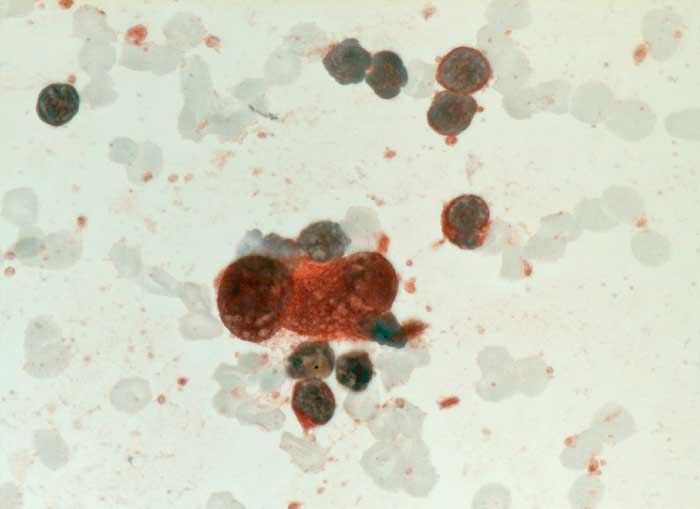

Hodgkin Lymphom: Reed-Sternberg Zelle

Feinnadelpunktion Lymphknoten cervikal links: Die grosse zweikernige Reed-Sternberg Zelle ist positiv für CD30.

Histologisch Hodgkin Lymphom, Mischzelltyp.

Zytologische Diagnose: Malignes Hodgkin-Lymphom.

Befund spricht am ehesten für ein klassisches Hodgkin-Lymphom vom Mischtyp. Die genaue histologische Klassifikation sollte jedoch am histologischen Präparat erfolgen.

CD30 (Ki-1)

630